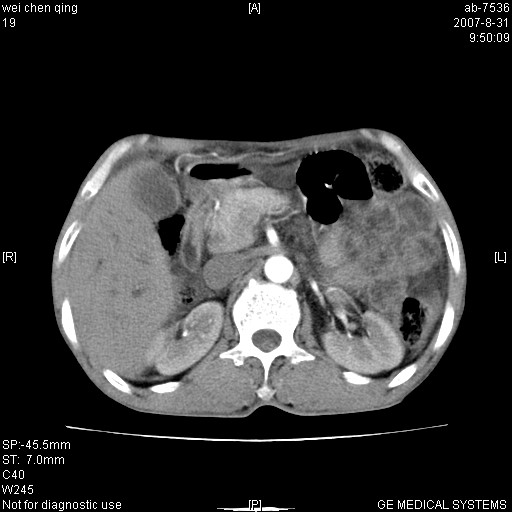

以下是引用zjzjr在2007-8-31 14:38:00的发言:[br]胰头癌伴肝内胆管扩张可能性大。

以下是引用zyyzzy在2007-8-31 14:34:00的发言:[br]该病人肝内胆管扩张,胆囊及胆总管未见明显扩张。在倒数第9层图像上可看到左右肝管结合部(肝总管)有软组织影,此处应薄层扫描。考虑肝总管占位(ca)、腹水。[br]